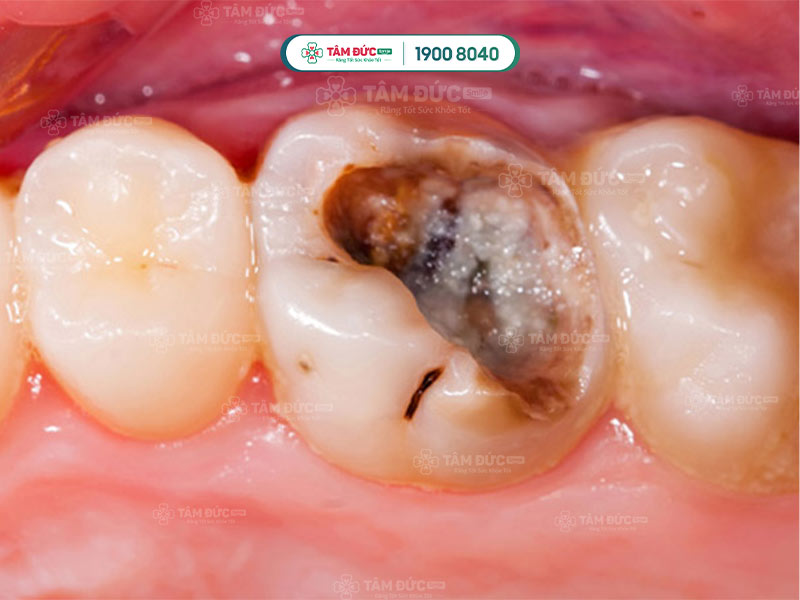

Ống tuỷ răng bị thoái hoá, làm cho thân răng chuyển sang màu vàng, nâu hoặc đen.